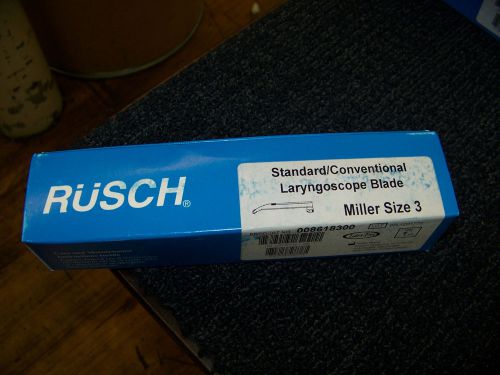

Rusch Laryngoscope Bulbs Frosted Size Large # 008628300 New

Rusch Standard/Conventional Laryngoscope Blade Miller Size 3 008618300 New